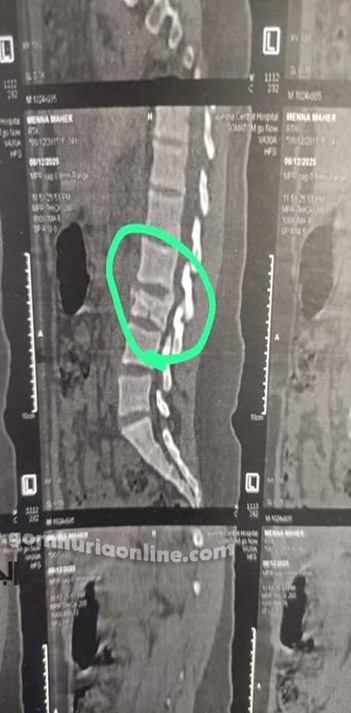

فتاة في الـ17 تنجو من خطر الشلل بعد سقوط مروع

في استجابة طبية عاجلة، استقبلت طوارئ المستشفى مريضة تبلغ من العمر 17 عامًا، إثر سقوطها من الطابق الثالث. وبعد الفحوصات، تبيّن وجود كسر مفتت بالفقرة القطنية الثالثة وضغط حاد على النخاع الشوكي.

تم إدخال المريضة لغرفة العمليات فورًا، حيث أُجريت لها جراحة دقيقة لتثبيت الفقرات وتوسيع القناة العصبية وإزالة الضغط، في عملية استغرقت ساعة واحدة وتكللت بالنجاح، مما أنقذها من شلل دائم.